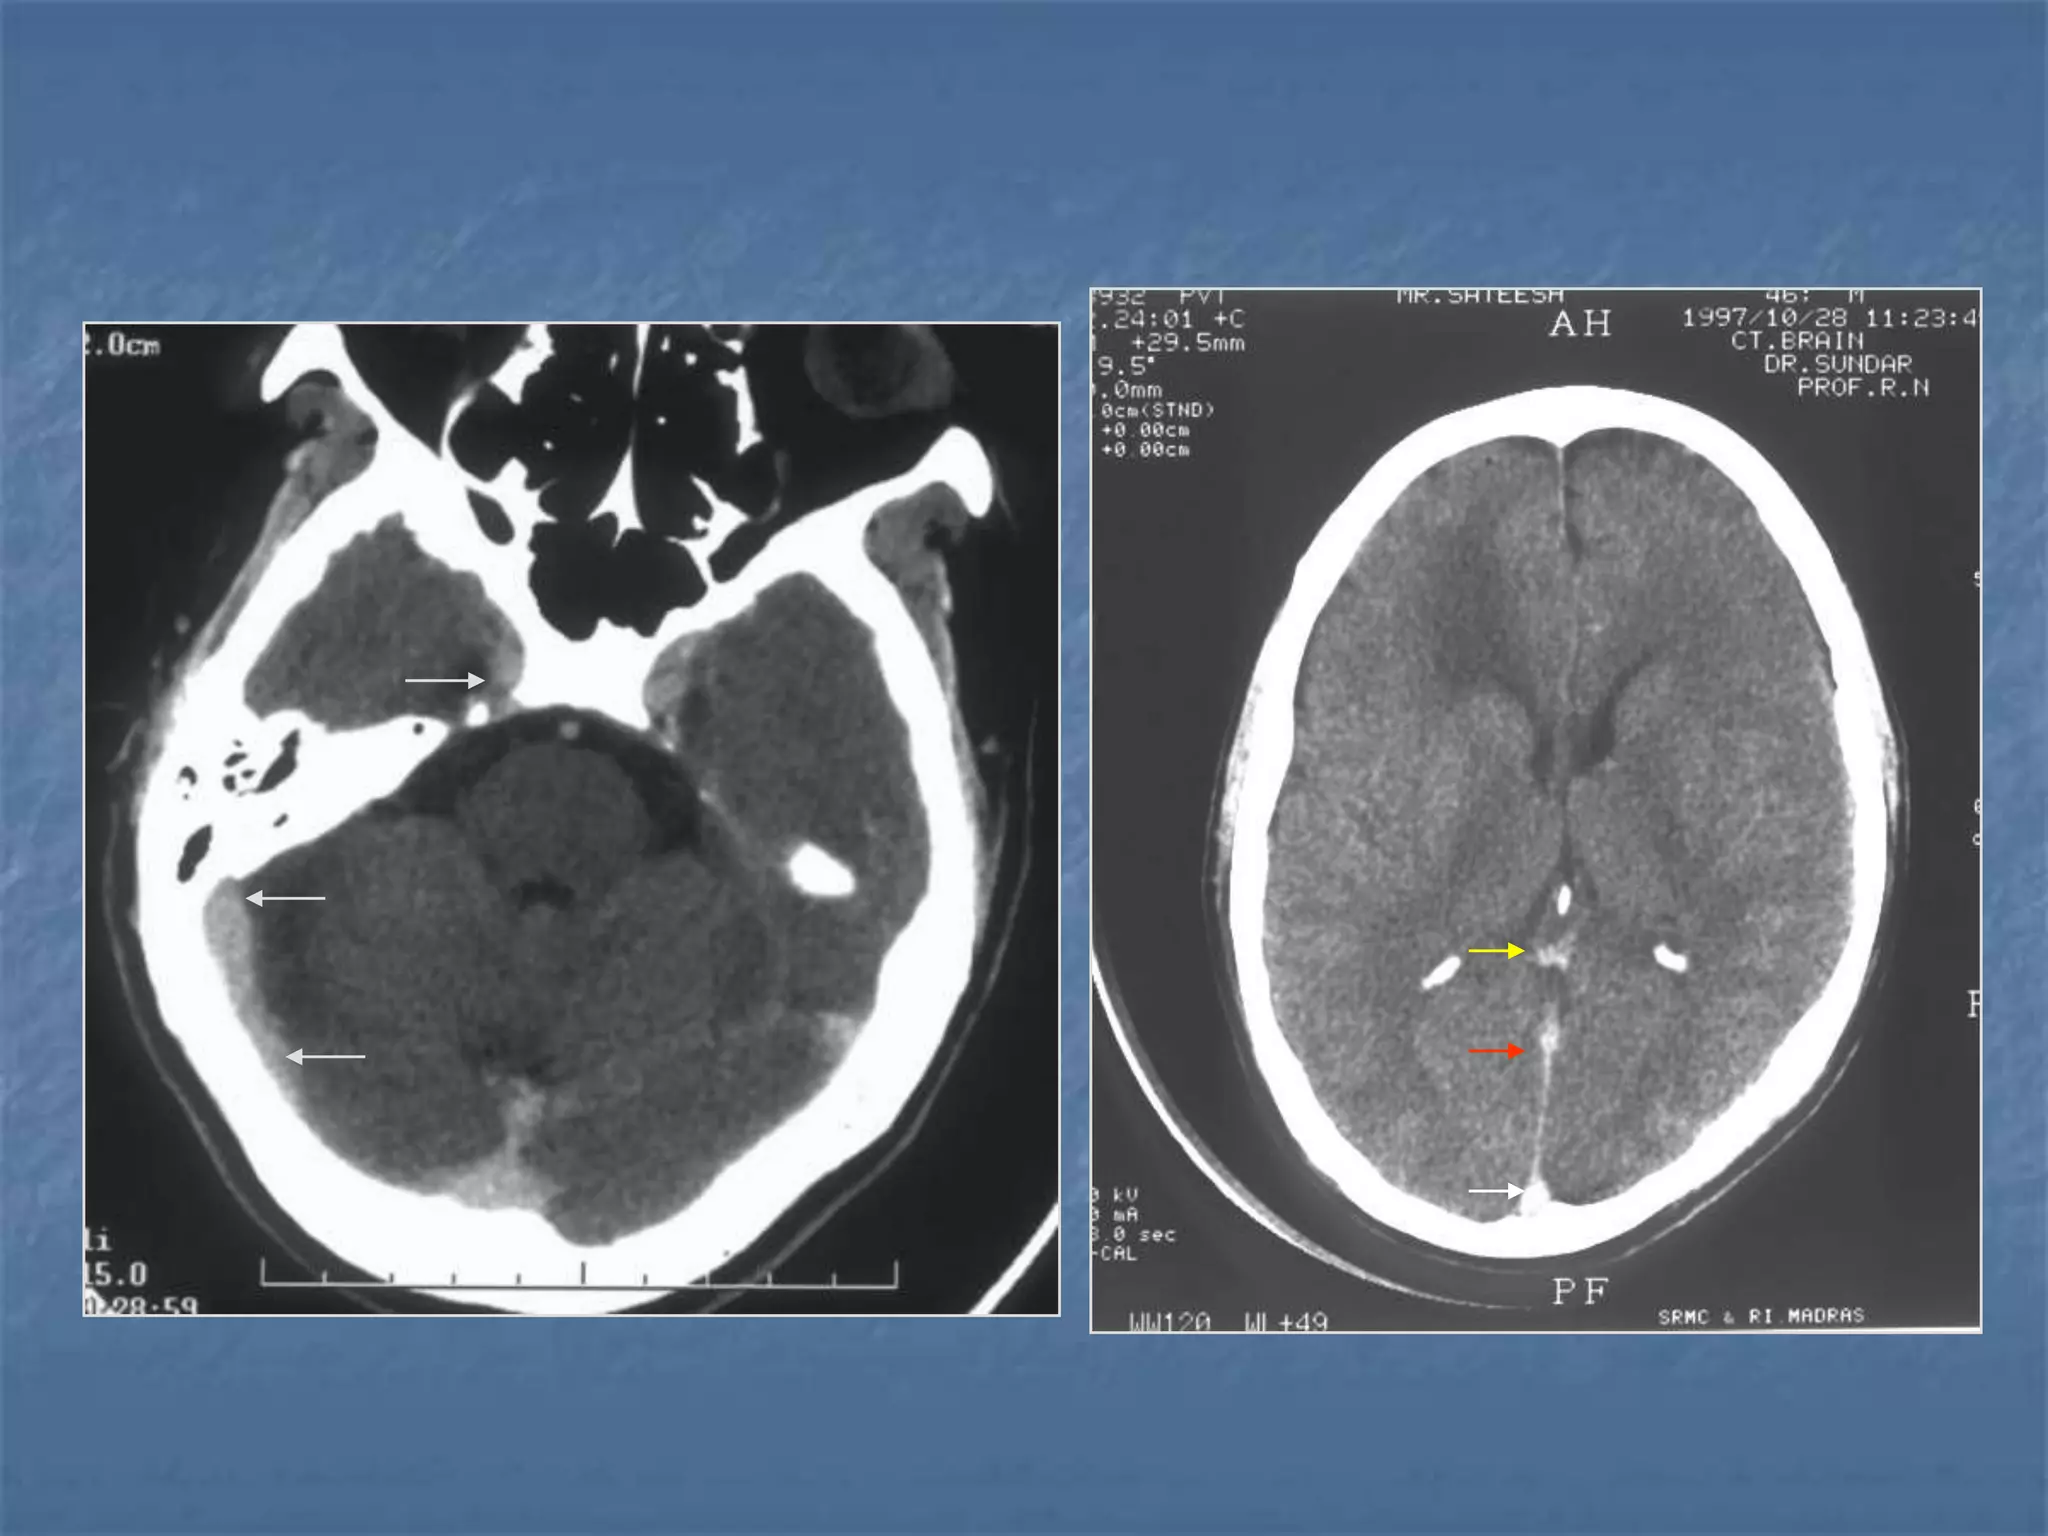

Subarachnoid hemorrhage

 In the absence of trauma, the most common cause

of subarachnoid hemorrhage is a ruptured cerebral

aneurysm. Cerebral aneurysms tend to occur at

branch points of intracranial vessels and thus are

frequently located around the Circle of Willis.

Common aneurysm locations include the anterior

and posterior communicating arteries, the middle

cerebral artery bifurcation and the tip of the basilar

artery. Subarachnoid hemorrhage typically presents

as the "worst headache of life" for the patient.

Detection of a subarachnoid hemorrhage is crucial

because the rehemorrhage rate of ruptured

aneurysms is high and rehemorrhage is often fatal.

 CT is currently the imaging modality of choice because

of its high sensitivity for the detection of subarachnoid

hemorrhage. CT is most sensitive for acute

subarachnoid hemorrhage. After a period of days to

weeks CT becomes much less sensitive as blood is

resorbed from the CSF. If there is a strong clinical

indication, LP may be warranted despite a negative CT

since small bleeds can be unapparent on imaging.

On CT, a subarachnoid hemorrhage appears as high

density within sulci and cisterns. The insular regions

and basilar cisterns should be carefully scrutinized for

subtle signs of subarachnoid hemorrhage.

Subarachnoid hemorrhage may have associated

intraventricular hemorrhage and hydrocephalus.